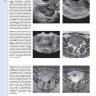

Книга содержит большое количество тщательно отобранных рисунков и фотографий с комментариями, которые показывают взаимосвязь между различными методами лучевой диагностики в гинекологии (УЗИ, эхогистерографией, МСКТ, МРТ, ПЭТ/КТ) и макроскопической картиной.

Примеры страниц из книги "Диагностическая визуализация в гинекологии: в трех томах". Том 2 - Шаабан А. М.